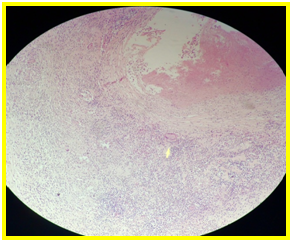

CT scan with contrast revealed a segmental thickening of the last ileal loops, distended small bowel loops without a detectable transition point, a 2 cm mesenteric mass associated with many mesenteric lymph nodes and magma of ileal loops some of which were contiguous to the sigmoid colon in the pelvis (Figure 1).

Figure1: A CT scan with contrast revealed a segmental thickening of the last ileal loops and distended small bowel loops without a detectable transition point.